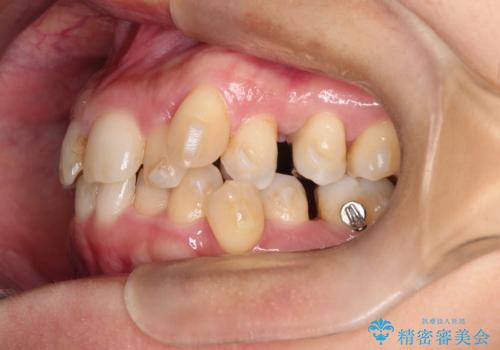

【インビザライン】重度叢生をなおしたい

- 全体的に歯並びをなおしたいことを主訴に来院されました。

上顎前歯が舌側傾斜していたため少し拡大を行いながら非抜歯で治療を行っています。

マウスピースをしっかり使用していただいたので、きれいな歯並びになりました。